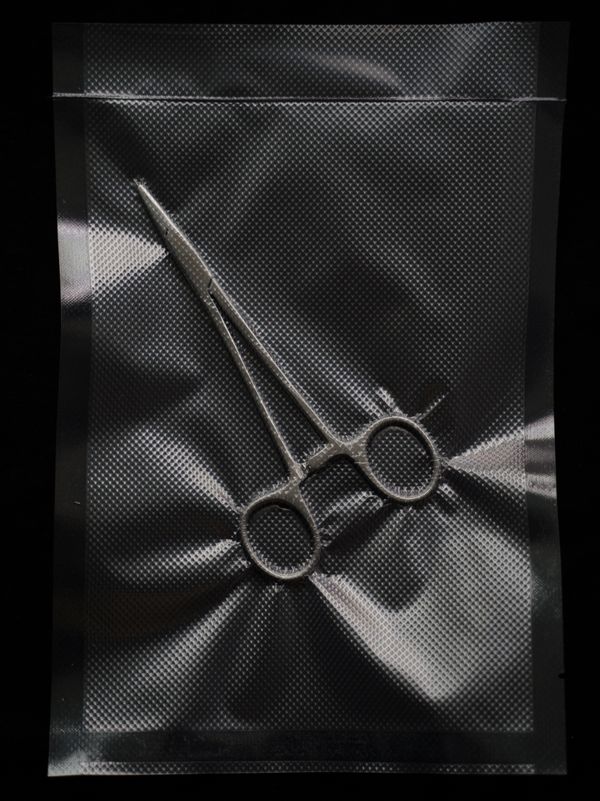

The entire project consists of a variety of materials, including secondary processed archival images, fashion magazine images of blister packs and affixed brackets, digitally processed archives of perfect occlusal curves, and conceptualized images that interact with simple devices. Starting from early and recent images of cosmetic dentistry, the project attempts to appropriated and secondary creations to visualize the invisible power of cosmetic dentistry, and ultimately leads to an established future where the incorruptible orthodontic bracket becomes a brand new organ of the human being.